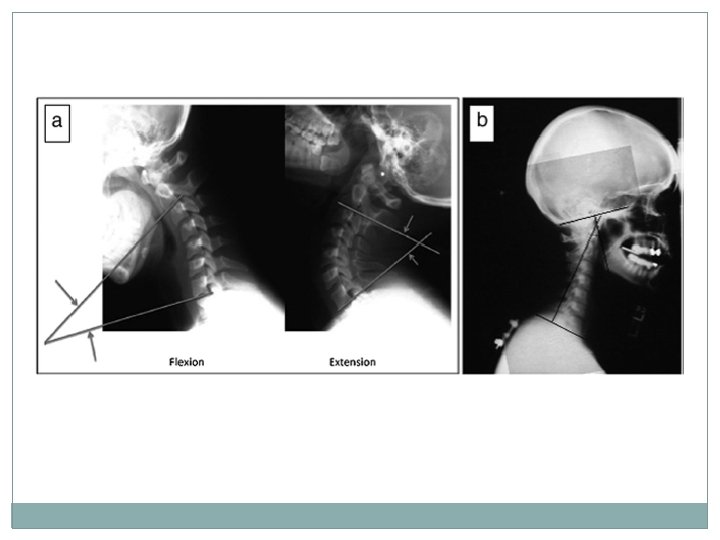

Normal Flexion-Extension

Abnormal Flexion-Extension �Biomechanics of FE was evaluated in cadaveric study in 1975 Specimens were placed under physiologic loads and ligamentous structures were damaged one by one until the cspine became unstable Determined criteria for abnormal FE � >3. 5 mm horizontal displacement � >11° angulation between adjacent vertebrae